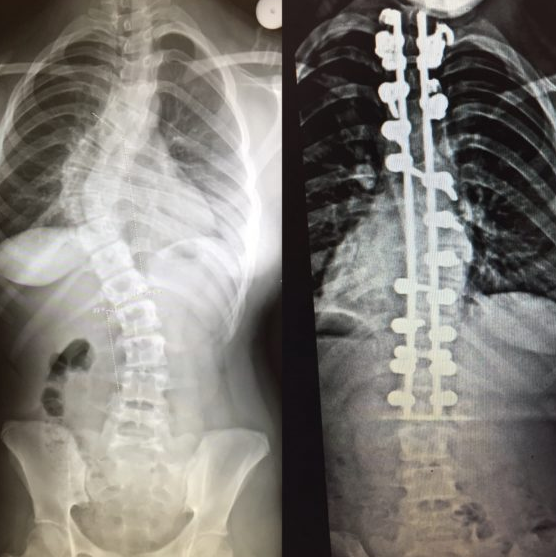

scoliosis findings: (3)

asymmetry in scapula, ribs, flanks, shoulder, hips

bad fitting clothes (one leg shorter than other)

more common in females (8-15 y/o)

scoliosis tx: (2)

bracing: slows curvature

surgery: spinal fusion w/ rod placement if severe (>45 degrees)